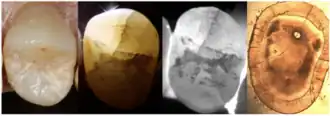

4. Transillumination

Transillumination involves using fiber-optic light to illuminate the tooth surface, with light diffraction at the crack helping to locate it (Chanchala HP et al., 2022).